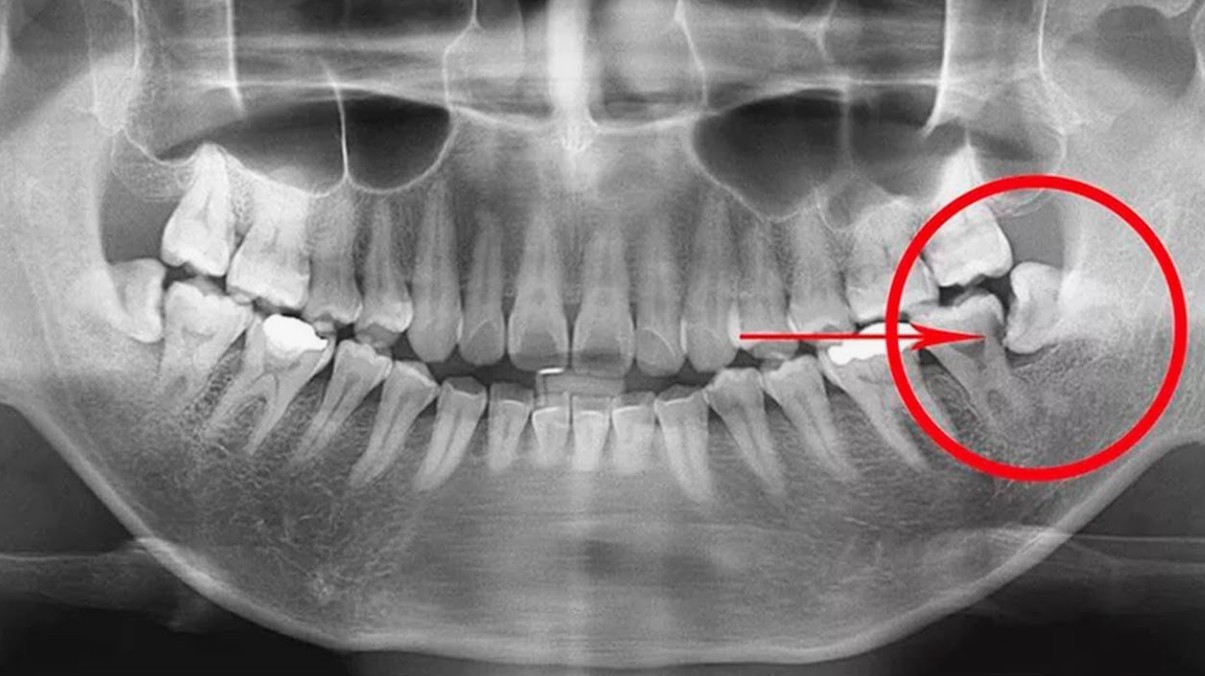

Tuy nhiên, trong một số trường hợp, răng khôn vẫn tồn tại dưới nướu mà không mọc lên. Để biết chính xác, nha sĩ có thể chỉ định chụp phim X-quang toàn hàm (panoramic). Kết quả sẽ cho thấy có mầm răng khôn hay không, và vị trí của nó có nguy cơ gây hại gì cho cấu trúc răng kế cận.

- Ảnh hưởng răng kế cận: Răng khôn mọc lệch có thể đẩy vào răng số 7, gây tiêu xương, sâu răng hoặc sai khớp cắn.

- Răng mọc ngầm, mọc lệch, hoặc đâm vào răng bên cạnh.